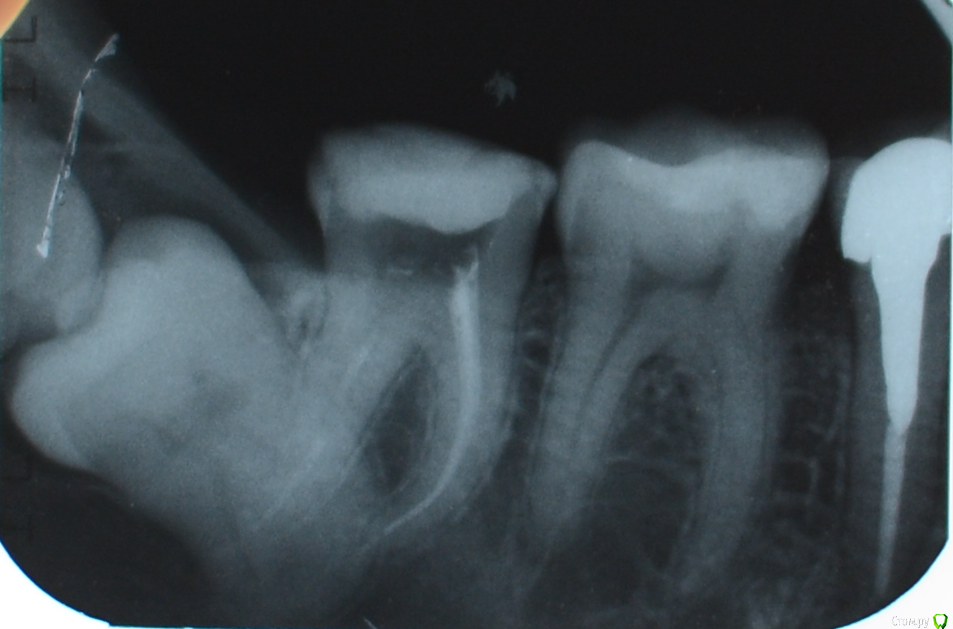

Kitten Опубликовано 13 декабря, 2014 Поделиться Опубликовано 13 декабря, 2014 (изменено) Добрый день, уважаемые специалисты Хочу с Вами проконсультироваться по сложному вопросу, за который не стали браться в платной клинике. После лечения глубокого кариеса зуба 4-7 остались две тонкие стенки, и я решила перейти к его протезированию. Перед установкой металлической вкладки сделали снимок, и оказалось, что зуб мудрости (или 8-ой зуб) лежит вертикально и цепляется корнями за семерку (снимок прилагается). А еще над семеркой есть "капюшон" (возможно, это тоже важная информация).8-ой зуб меня, в принципе, не беспокоит, десна не воспалена. Только иногда, когда думаю о нем, он как будто немножко ноет и "прорезаться" хочет. Хотя это мой мозг, возможно :-)Ортопед сказал, что без согласования хирурга протезировать зуб не будет, а местный хирург браться за мой случай не захотел, как я уже сказала. Посоветуйте, пожалуйста, что делать с восьмеркой: переходить к протезированию 7 зуба и не думать о нем или все-таки удалить. Если подскажите, куда можно обратиться по этому вопросу, буду признательна. Спасибо! Изменено 13 декабря, 2014 пользователем Kitten Ссылка на комментарий

red_butler Опубликовано 13 декабря, 2014 Поделиться Опубликовано 13 декабря, 2014 у Вас там два зуба, делайте Кт и ищите грамотного хирурга и удаляйте оба до протезирования седьмого. Случай интересный 4 Ссылка на комментарий

Зубоволок 36 Опубликовано 13 декабря, 2014 Поделиться Опубликовано 13 декабря, 2014 у Вас там два зуба, делайте Кт и ищите грамотного хирурга и удаляйте оба до протезирования седьмого. Случай интересный Действительно похоже на то что и девятка имеется. Ссылка на комментарий